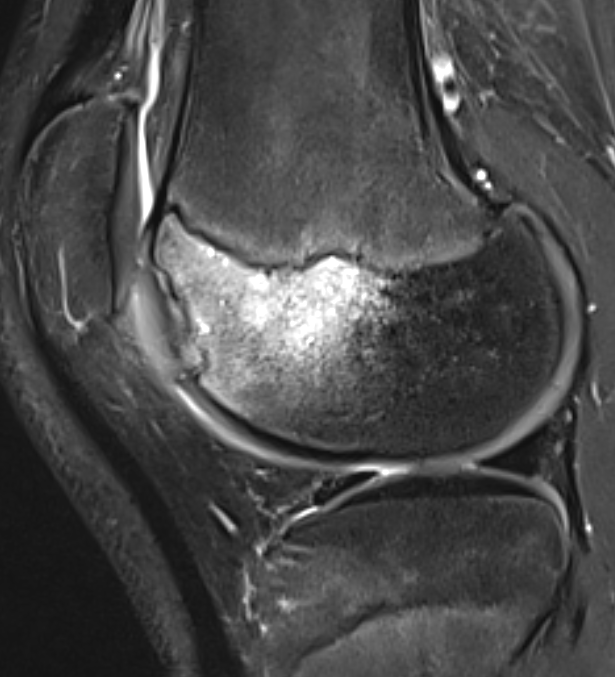

MRI Classification

Stage 1: Low signal changes, articular cartilage intact (stable)

Stage 2: Articular cartilage breached, low signal indicating fibrocartilage behind fragment (stable)

Stage 3: Articular cartilage breached, high signal indicating synovial fluid behind fragment (unstable)

Stage 4: Loose body (unstable)

Look for

- integrity of the articular cartilage

- fluid behind the lesion, suggesting instability

- displacement of the lesion

Stable

- no synovial fluid behind lesion

Unstable

- cartilage breach with synovial fluid behind lesion

Stage 1. Articular cartilage intact

Stage 2. Articular cartilage breach, but low signal intensity behind fragment

Stage 3. Articular cartilage breach and synovial fluid behind fragment (unstable)

Stage 4. Loose body

Minimally displaced loose body

Completely detached